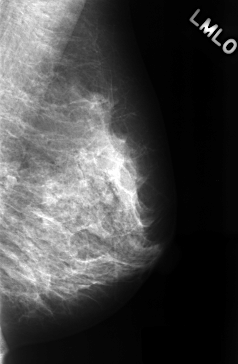

ics_version 1.0 filename C-0333-1 DATE_OF_STUDY 22 12 1995 PATIENT_AGE 44 FILM FILM_TYPE REGULAR DENSITY 2 DATE_DIGITIZED 12 10 1998 DIGITIZER LUMISYS LASER SEQUENCE LEFT_CC LINES 4480 PIXELS_PER_LINE 2904 BITS_PER_PIXEL 12 RESOLUTION 50 NON_OVERLAY LEFT_MLO LINES 4368 PIXELS_PER_LINE 2856 BITS_PER_PIXEL 12 RESOLUTION 50 NON_OVERLAY RIGHT_CC LINES 4456 PIXELS_PER_LINE 2864 BITS_PER_PIXEL 12 RESOLUTION 50 OVERLAY RIGHT_MLO LINES 4424 PIXELS_PER_LINE 2864 BITS_PER_PIXEL 12 RESOLUTION 50 OVERLAY |